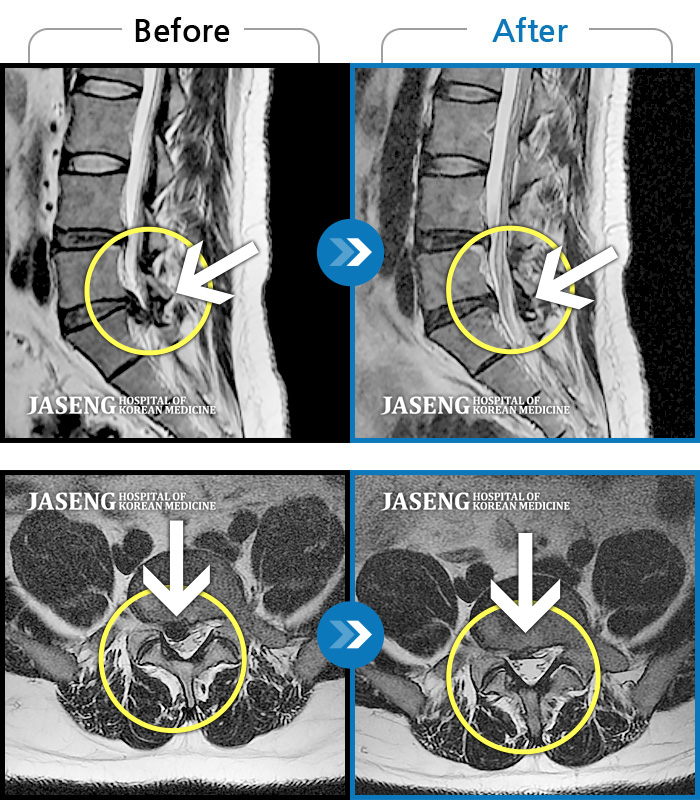

허리디스크

부천 · 신동재 원장

오른쪽 허리 골반 통증, 보행시 우측 다리까지 통증 및 당김 증상

촬영시기

2017.09.07 ~ 2018.12.07

2018.12.14